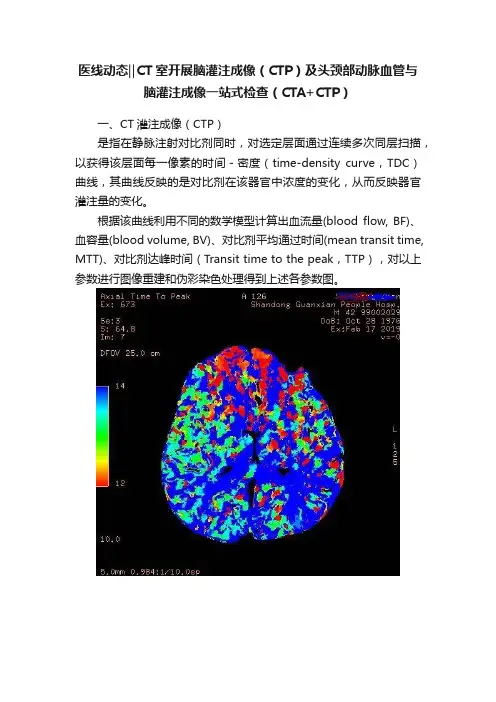

医线动态‖CT室开展脑灌注成像(CTP)及头颈部动脉血管与脑灌注成像一站式检查(CTA+CTP)一、CT灌注成像(CTP)是指在静脉注射对比剂同时,对选定层面通过连续多次同层扫描,以获得该层面每一像素的时间-密度(time-density curve,TDC)曲线,其曲线反映的是对比剂在该器官中浓度的变化,从而反映器官灌注量的变化。

根据该曲线利用不同的数学模型计算出血流量(blood flow, BF)、血容量(blood volume, BV)、对比剂平均通过时间(mean transit time, MTT)、对比剂达峰时间(Transit time to the peak,TTP),对以上参数进行图像重建和伪彩染色处理得到上述各参数图。